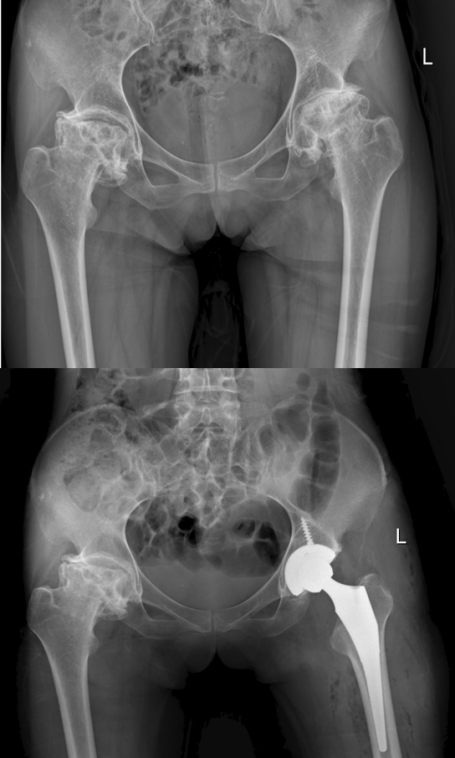

影像检查报告显示,张大姐双侧的股骨头已经发生了灾难性的完全塌陷,外形扭曲变扁,失去了正常的解剖形态,关节间隙几乎消失。

张还添教授团队为张大姐实施了“机器人辅助下全髋关节置换术”。术前,基于患者个性化的三维CT数据,机器人系统已规划出匹配度最高的假体型号、安装位置和角度,精度达到亚毫米级。术中,机器人的机械臂在医生的指挥下,协助完成对病变骨骼的精确打磨和假体的安放。

手术中,团队发现张大姐的股骨头形态怪异,严重变形,色泽暗沉,这是由于长期病损与缺血带来造成的,在机器人辅助下,病变的股骨头被精准移除,一个人工关节假体被植入预定位置,重建了髋关节正常的力学结构与旋转中心。更重要的是,整个手术过程出血少,对周围健康组织的创伤降到了最低。